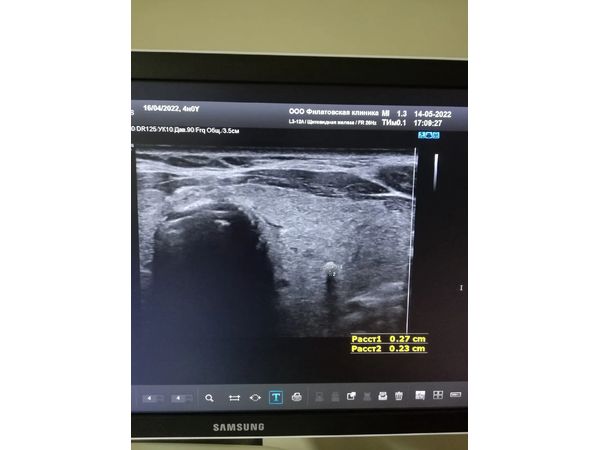

- TI-RADS 4б — округлое изоэхогенное образование размером 1,04×1,23 см с нечёткими, ровными контурами и единичным кальцинатом (0,27×0,23 см), умеренное кровоснабжение по периферии.